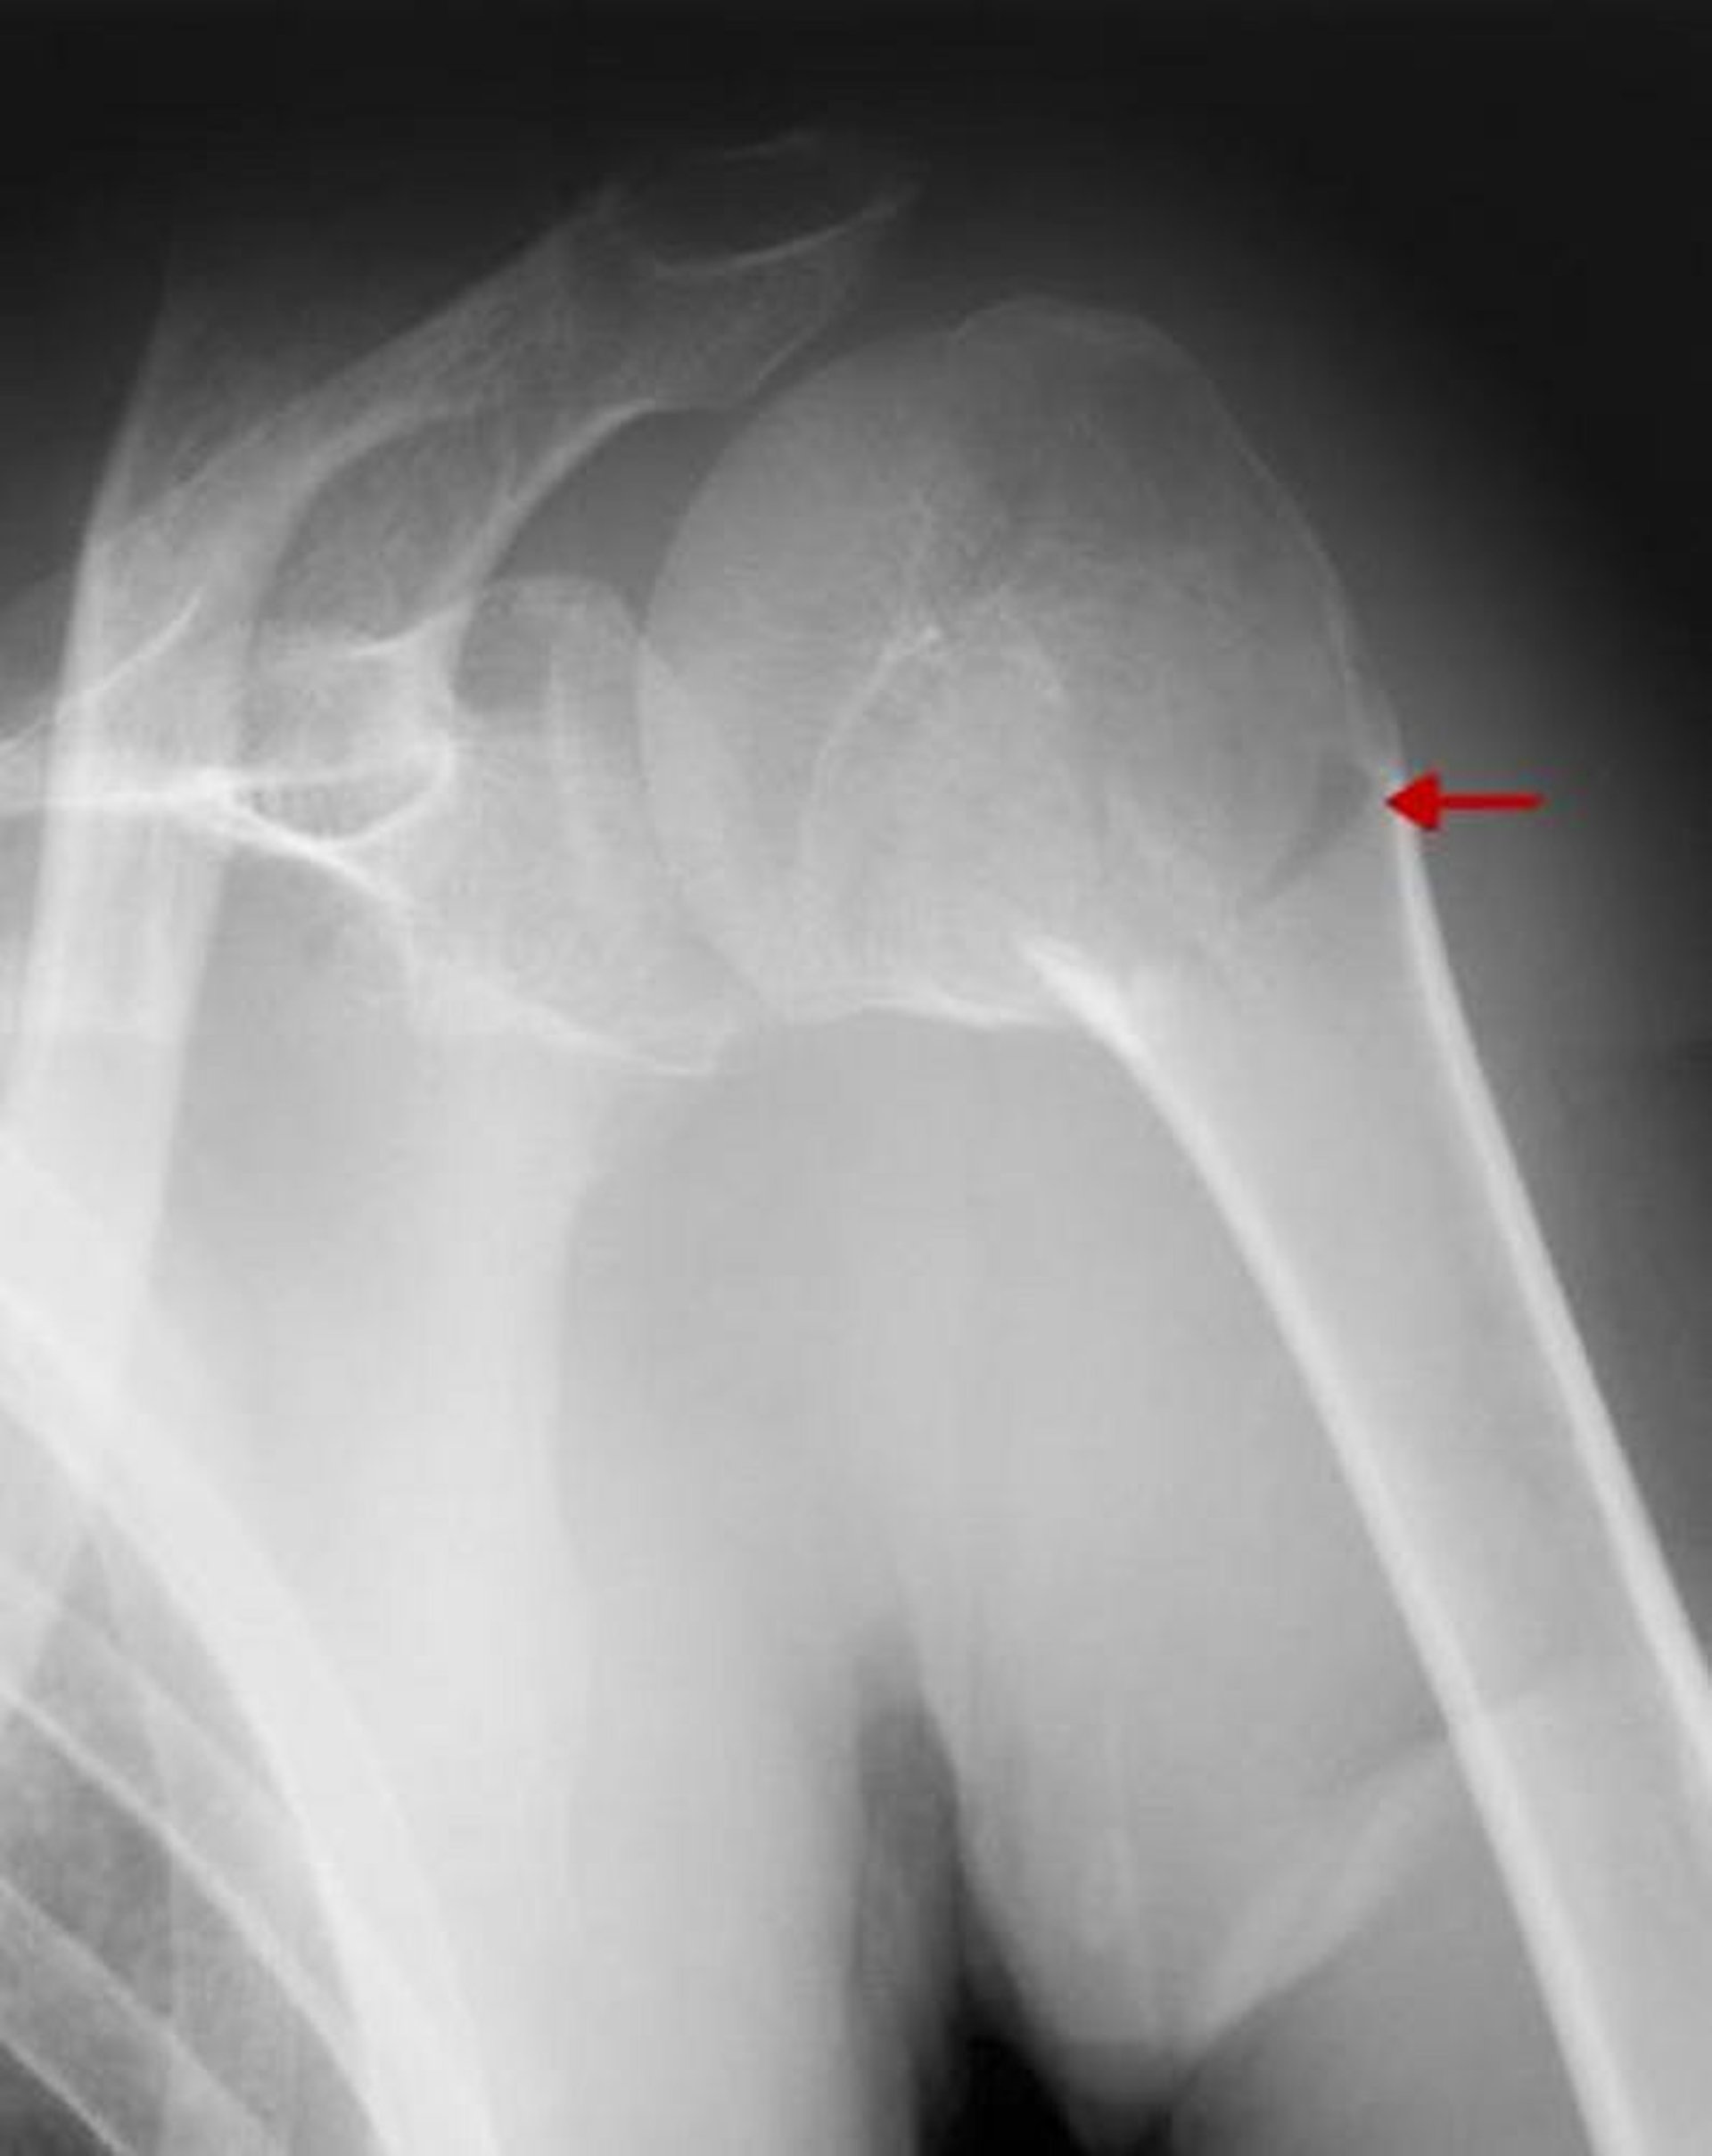

Fracture proximale de l'humérus

Cette fracture implique le cou chirurgical. Etant donné qu'il n'y a pas de déplacement ou d'angulation > 45°, il s'agit d'une fracture en une seule partie.